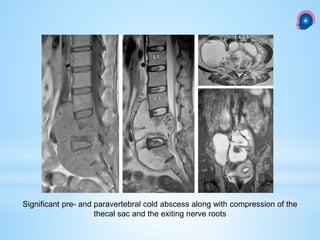

Significant pre- and paravertebral cold abscess along with compression of the

thecal sac and the exiting nerve roots